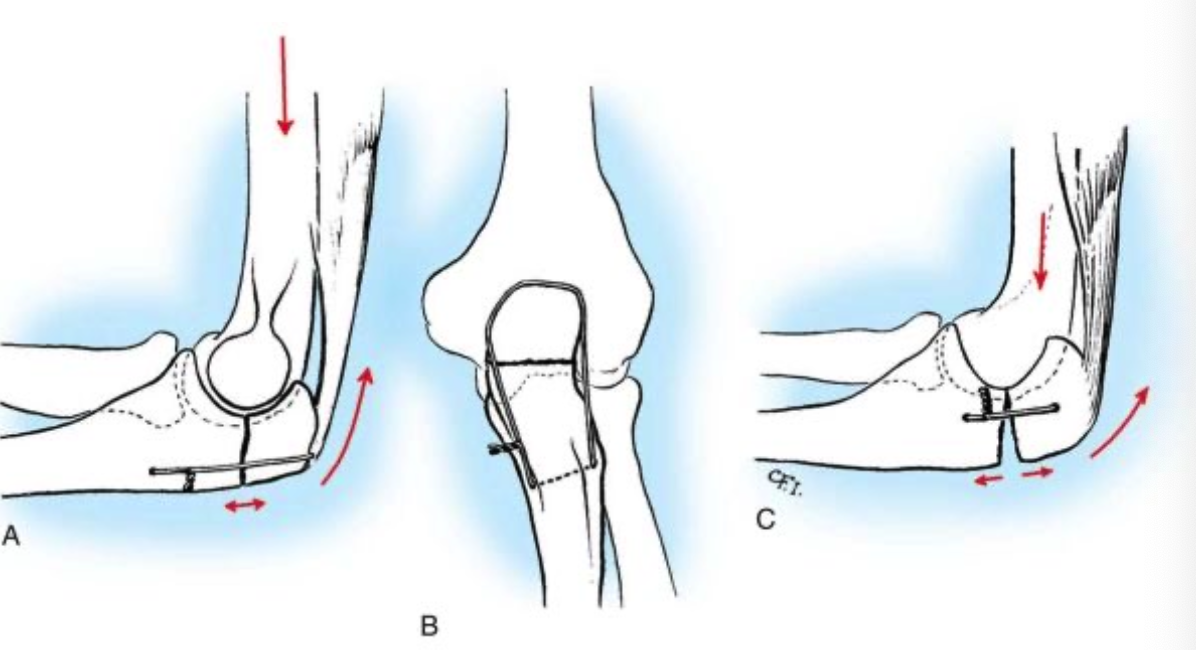

Локтевой перелом форум

Локтевой перелом форум 115 фото